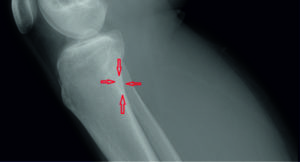

- Рентгенологическое обследование (рентген). Проводится для того, чтобы подтвердить диагноз. В данном случае проводится обследование сочленения в боковой проекции. На рентгеновском снимке видна остеохондропатия бугристости большеберцовой кости и ее фрагментация, если таковая имеется.